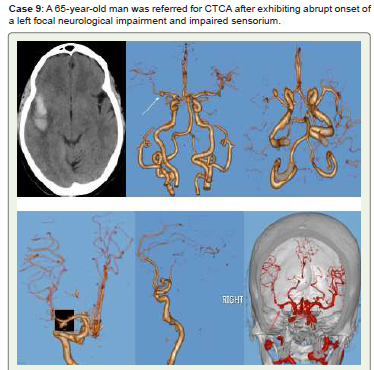

Figure 9:Right temporal lobe lobulated hematoma with surrounding edema

is visible on CT axial non-contrast (A), whereas right MCA (M1) saccular

aneurysm projecting inferiorly is visible on 3D-VR (B-E) and virtual dissection

(F) images. Treated consevatively & on regular follow up.